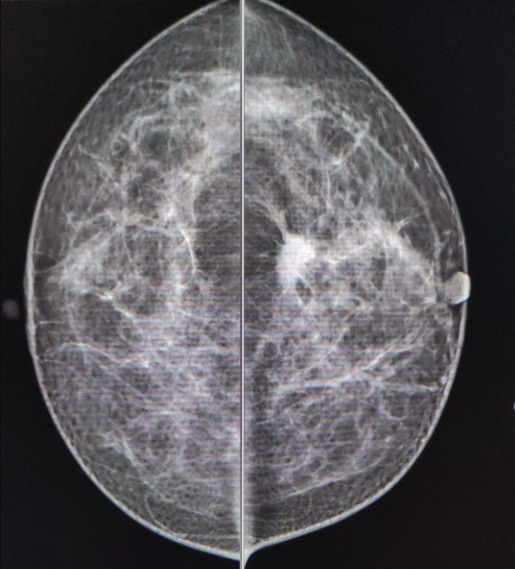

- La mastografía en mujeres entre 40 y 69 años.